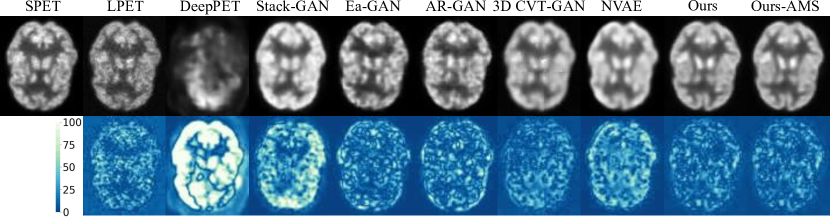

Refer to caption

Figure 3: Qualitative comparison on the in-house dataset using a cross-dataset experimental setup. The visual results demonstrate the high generalizability of our approach, which generates high-quality RPET images with the lowest residual error on an unseen dataset. Conversely, DeepPET method tends to overfit to the training dataset, leading to corrupted images on the in-house dataset. These results confirm the superior performance of our method in the challenging task of cross-dataset PET reconstruction.